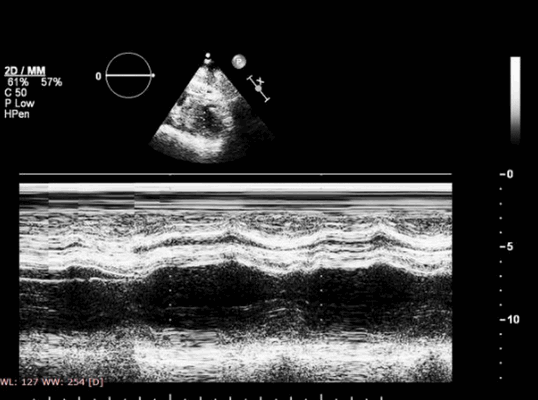

Указанные изменения можно обнаружить с помощью двумерной эхокардиографии, но M-режим также чрезвычайно хорош, поскольку его высокая частота дискретизации делает его очень чувствительным к движению стенок и аномалиям утолщения. Важно, чтобы курсор располагался под углом 90° к стенке. Есть ограниченные области миокарда ЛЖ, которые можно исследовать в М-режиме - наиболее полезно задняя стенка и МЖП. Изменения обратимы, если ишемия кратковременная, например в покое, прием антиангинальных препаратов, проведенная вовремя чрескожная транслюминальная коронарная ангиопластика, тромболизис или аортокоронарное шунтирование (АКШ). Если кровоснабжение миокарда прервано более чем на 1 час, происходят необратимые изменения, включающие инфаркт миокарда и рубцевание.

У всех больных для оценки показателей деформации МК измеряли величину систолического верхушечного прогиба створок МК — расстояние между точкой смыкания створок и плоскостью митрального кольца (h, см) (рис. 1).